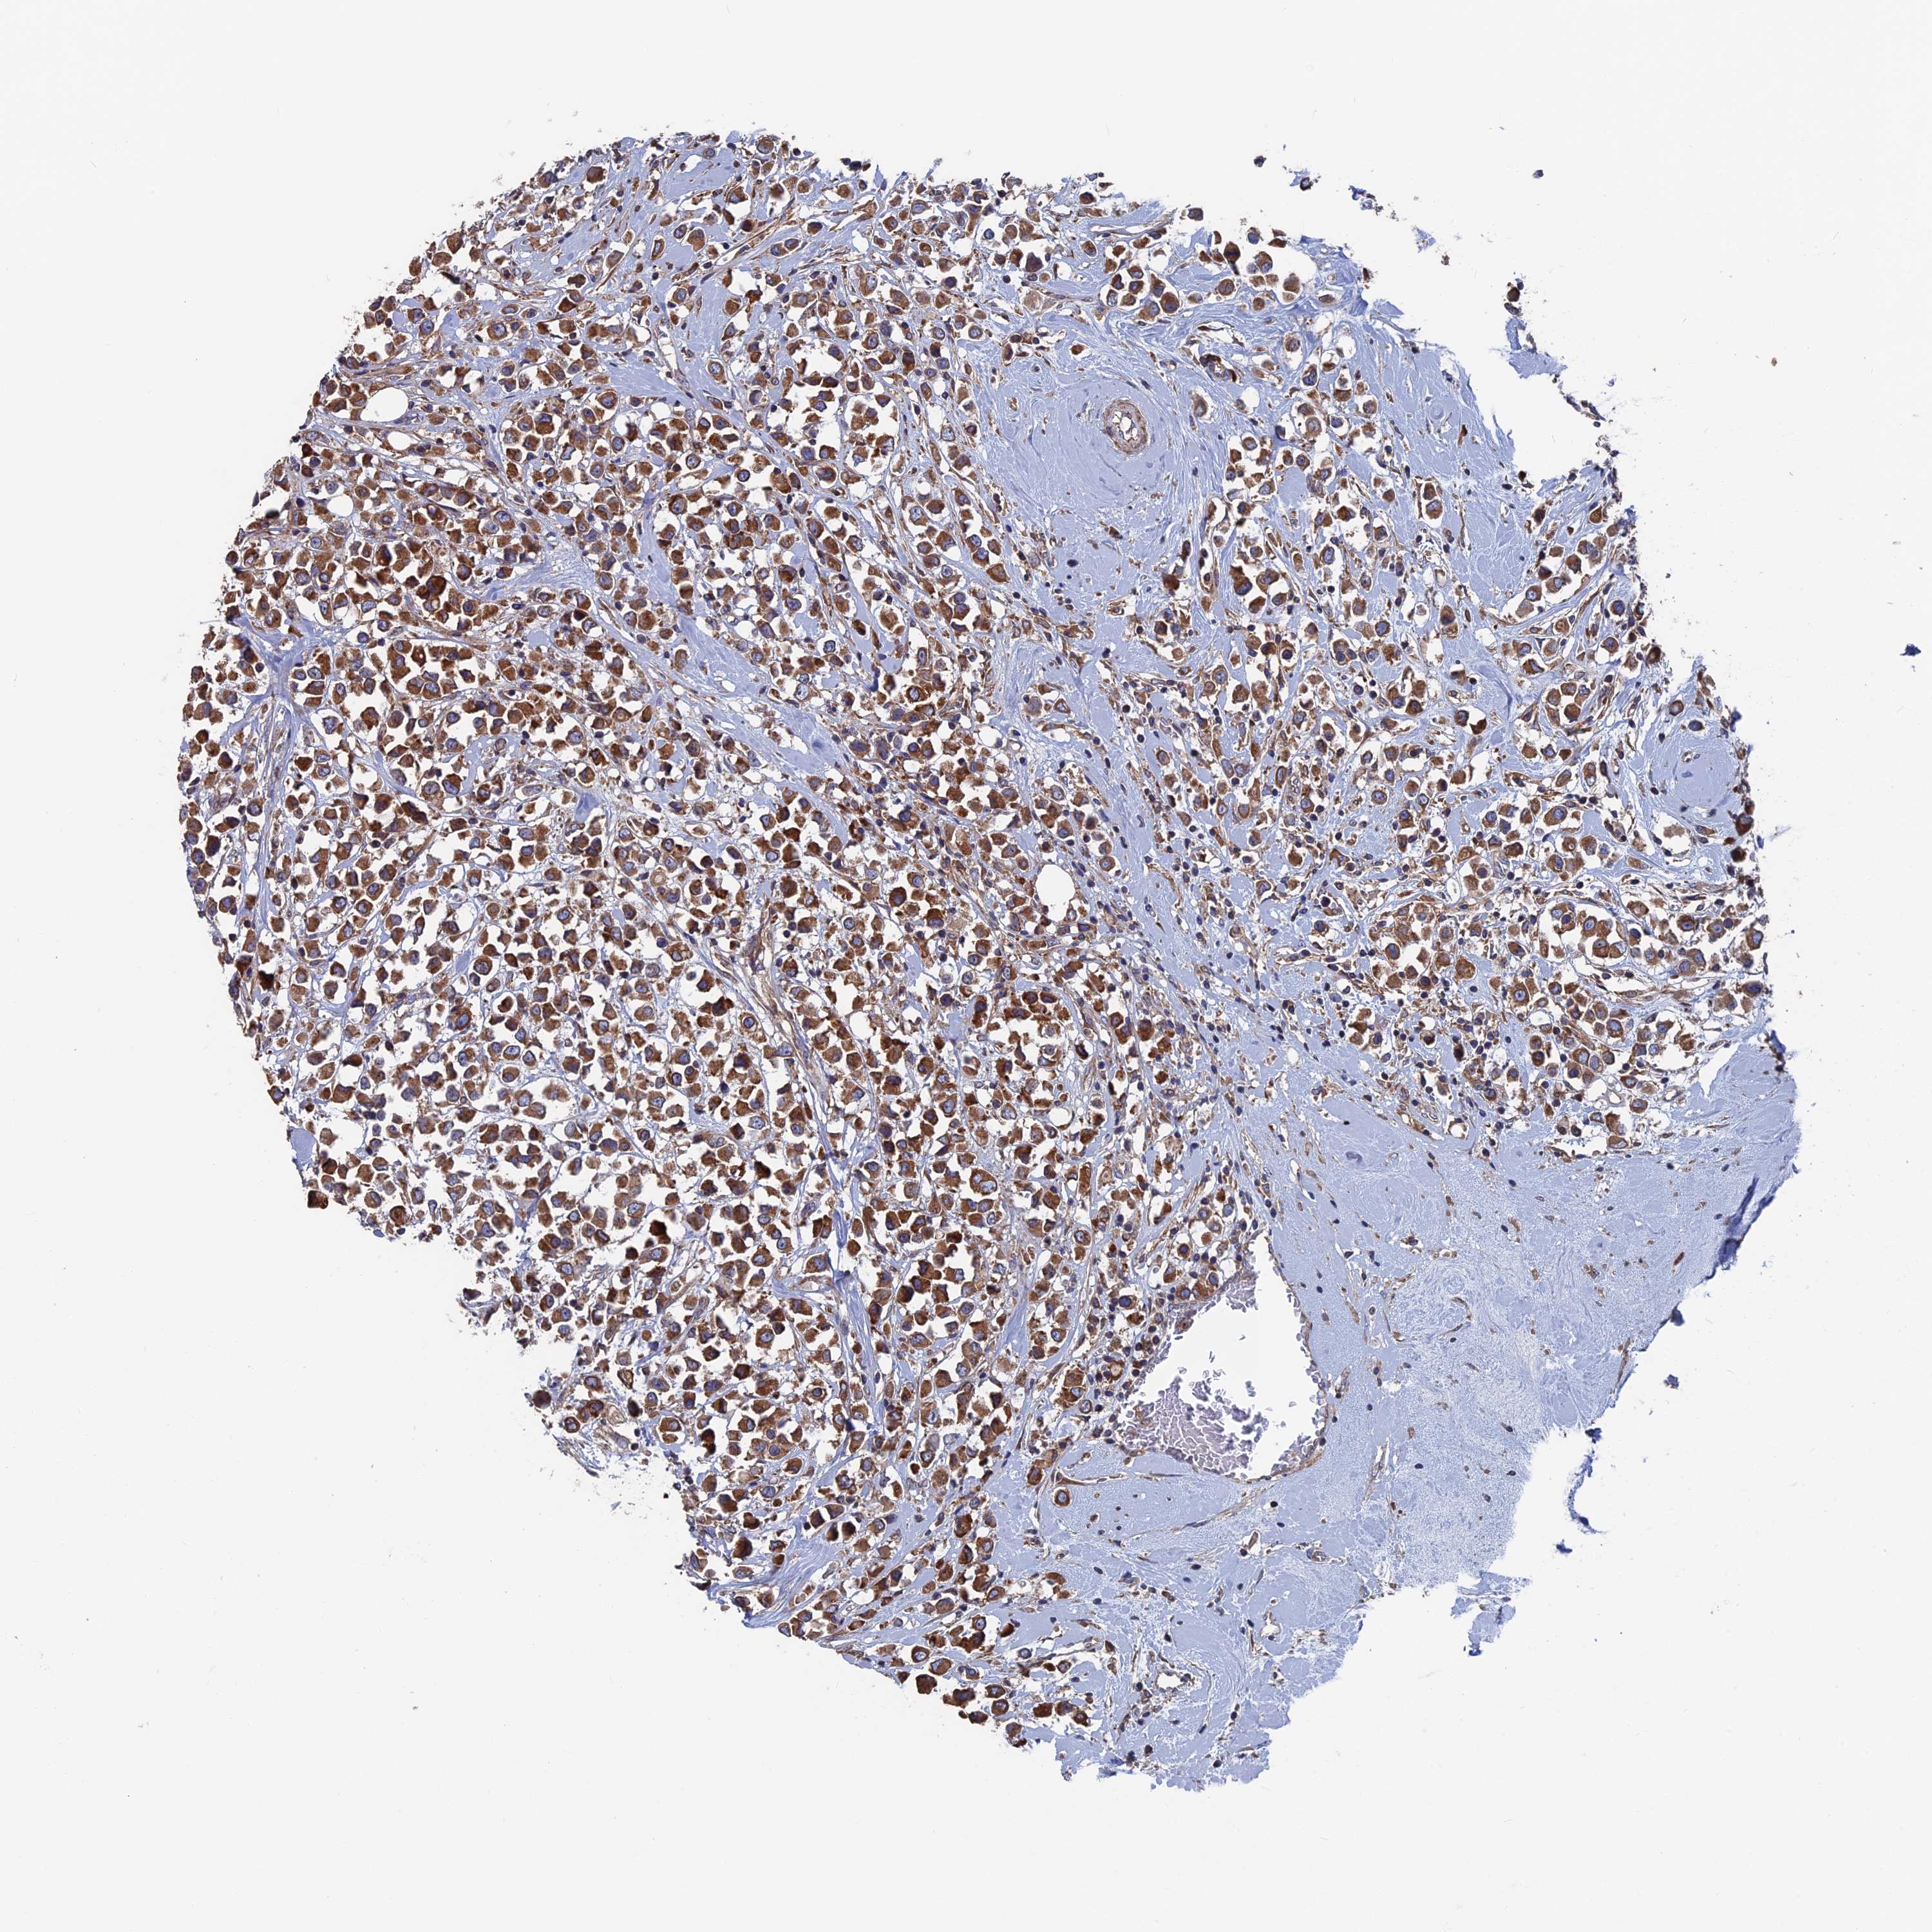

CANCER BREAST CANCER Show tissue menu

BRCA TCGA BRCA VALIDATION PROTEIN EXPRESSION